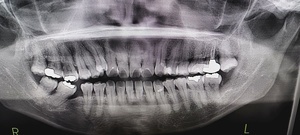

どうやって診断される?|検査・受診の流れを解説

歯科・口腔外科での診察方法

医師の視診で典型的な白斑や網目状の模様が観察されれば、口腔扁平苔癬と仮診断されることが多いです。

組織検査(生検)が必要なケースとは?

白斑が厚く、患部が硬い、出血しやすい

痛みが強く、潰瘍がある

がん化のリスクを排除したい場合

このような場合には粘膜の一部を採取する生体検査(生検)が行われます。